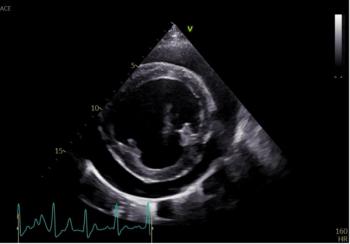

The transcatheter edge-to-edge repair procedure is a minimally invasive treatment for mitral regurgitation.

Unlocking insights into diagnosis, treatment, and prognosis in small animal cardiology